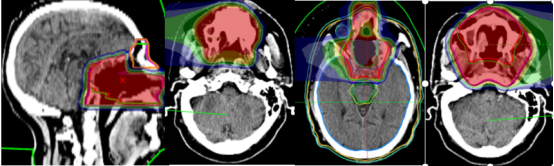

Figure 3: Target Field Design

Figure 4: Carbon Ion Radiotherapy Comparison